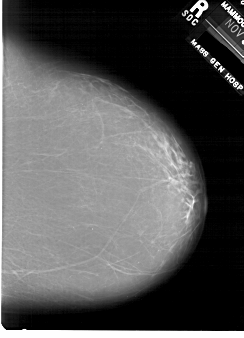

A_1876_1.RIGHT_CC

RIGHT_CC LINES 6421 PIXELS_PER_LINE 4621 BITS_PER_PIXEL 12 RESOLUTION 43.5 NON_OVERLAY